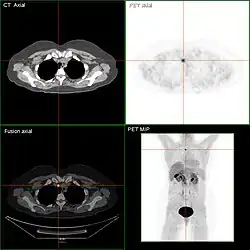

Nach sechs bis zwölf Monaten (frühestens nach drei Monaten) sollte in bestimmten Fällen das Ergebnis der Radiojodtherapie mit einer sogenannten Radiojoddiagnostik dokumentiert werden.[18][19] Im Hormonentzug (vier Wochen vor der Untersuchung keine Einnahme des L-Thyroxins) wird eine geringe Menge Jod-131 verabreicht und die Verteilung im Körper nach 48 Stunden mit einer Szintigraphie ermittelt. Auch für diese Radiojoddiagnostik ist – hier bereits seit 2001 – ein Hormonentzug nicht mehr notwendig (s. o.). Bei dem Einsatz von rhTSH zur Vorbereitung einer Radiojoddiagnostik muss allerdings bedacht werden, dass für eine eventuell notwendige erneute Radiojodtherapie auch das rhTSH erneut verabreicht werden muss.